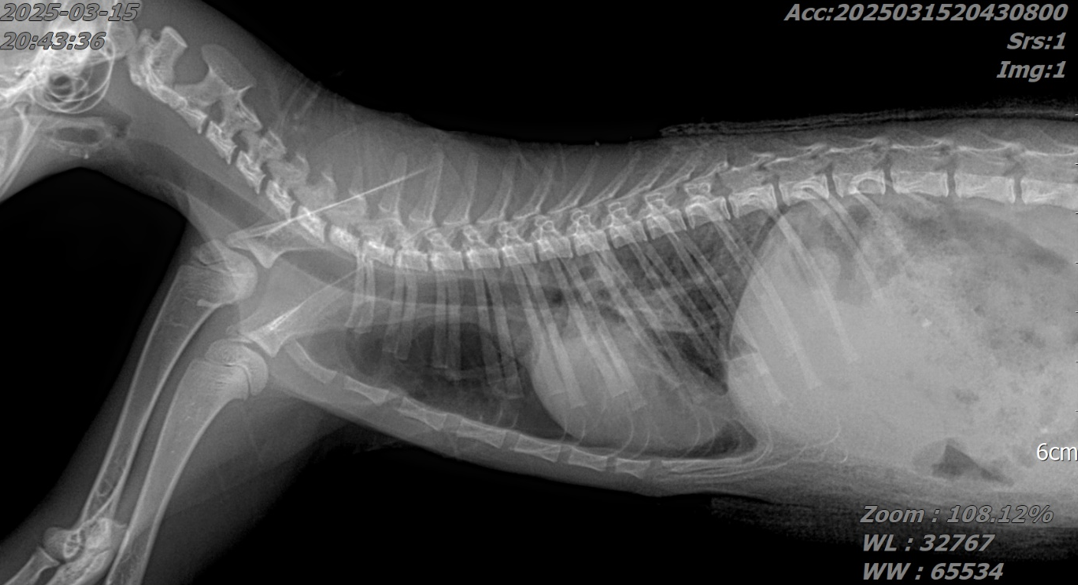

흉부 및 복부 X-ray를 촬영한 결과 흉수 및 복수가 모두 확인되었으며 심장 주변에 복강 장기들이 들어차면서 폐가 허탈되어 있는 모습을 확인할 수 있었습니다.

특히 폐 음영이 정상적으로 나타나는 부위가 없어, 호흡 곤란의 원인을 쉽게 확인할 수 있었습니다.